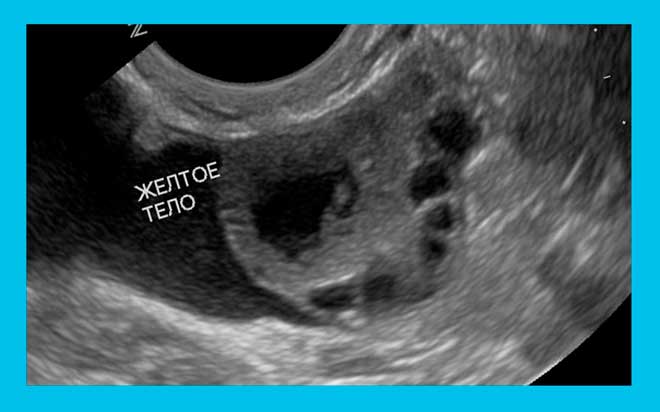

Желтое тело на УЗИ

Разглядеть желтое тело на УЗИ можно только на 3 день после овуляции. Если произошло оплодотворение, ЖТ должно хорошо визуализироваться. Его отсутствие сразу насторожит врача.

Ультразвуковое исследование беременных проводят как раз для того, чтобы выявить несколько параметров, в том числе оценить размеры желтого тела, определить количество ЖТ. Всё это необходимо, чтобы судить насколько нормально развивается плод. Также следует узнать (с помощью анализов), достаточно ли гормона прогестерона вырабатывается, чтобы эта беременность сохранилась.

УЗИ назначают и не беременным, чтобы понять: возможно ли оплодотворение, запускаются ли процессы овуляции и т.д. Исследование позволяет узнать: созрела ли яйцеклетка, в каком яичнике произошло созревание, произошла ли овуляция, есть ли ЖТ и справляется ли оно со своими функциями. Однако нет возможности по размерам ЖТ определить, когда именно произошла овуляция, только примерный срок.

Если беременности нет и ЖТ не обнаружено, значит врач констатирует: овуляции не было. В норме такое может происходит до 2 раз в год в репродуктивном возрасте – 20-35 лет (у женщин от 35 – до 5-6 раз в год). Если беременности нет, но есть ЖТ – это также нормально: ЖТ существует автономно до двух недель.

УЗИст сразу смотрит, имеется ли плодное яйцо. Определив наличие и локализацию ЖТ в яичнике, специалист замеряет диаметр. В норме временное новообразование должно в диаметре достигать 12-30 мм.

Тело растёт и развивается, поэтому на каждой стадии своего развития должно быть разного размера: чем дальше от дня овуляции, тем больше ЖТ. При беременности оно существует до 10-16 недель. После этого срока ЖТ передаёт свои функции сформировавшейся плаценте и исчезает. Перед тем, как рассосаться, тело начинает уменьшаться (регресс заметен на УЗИ).